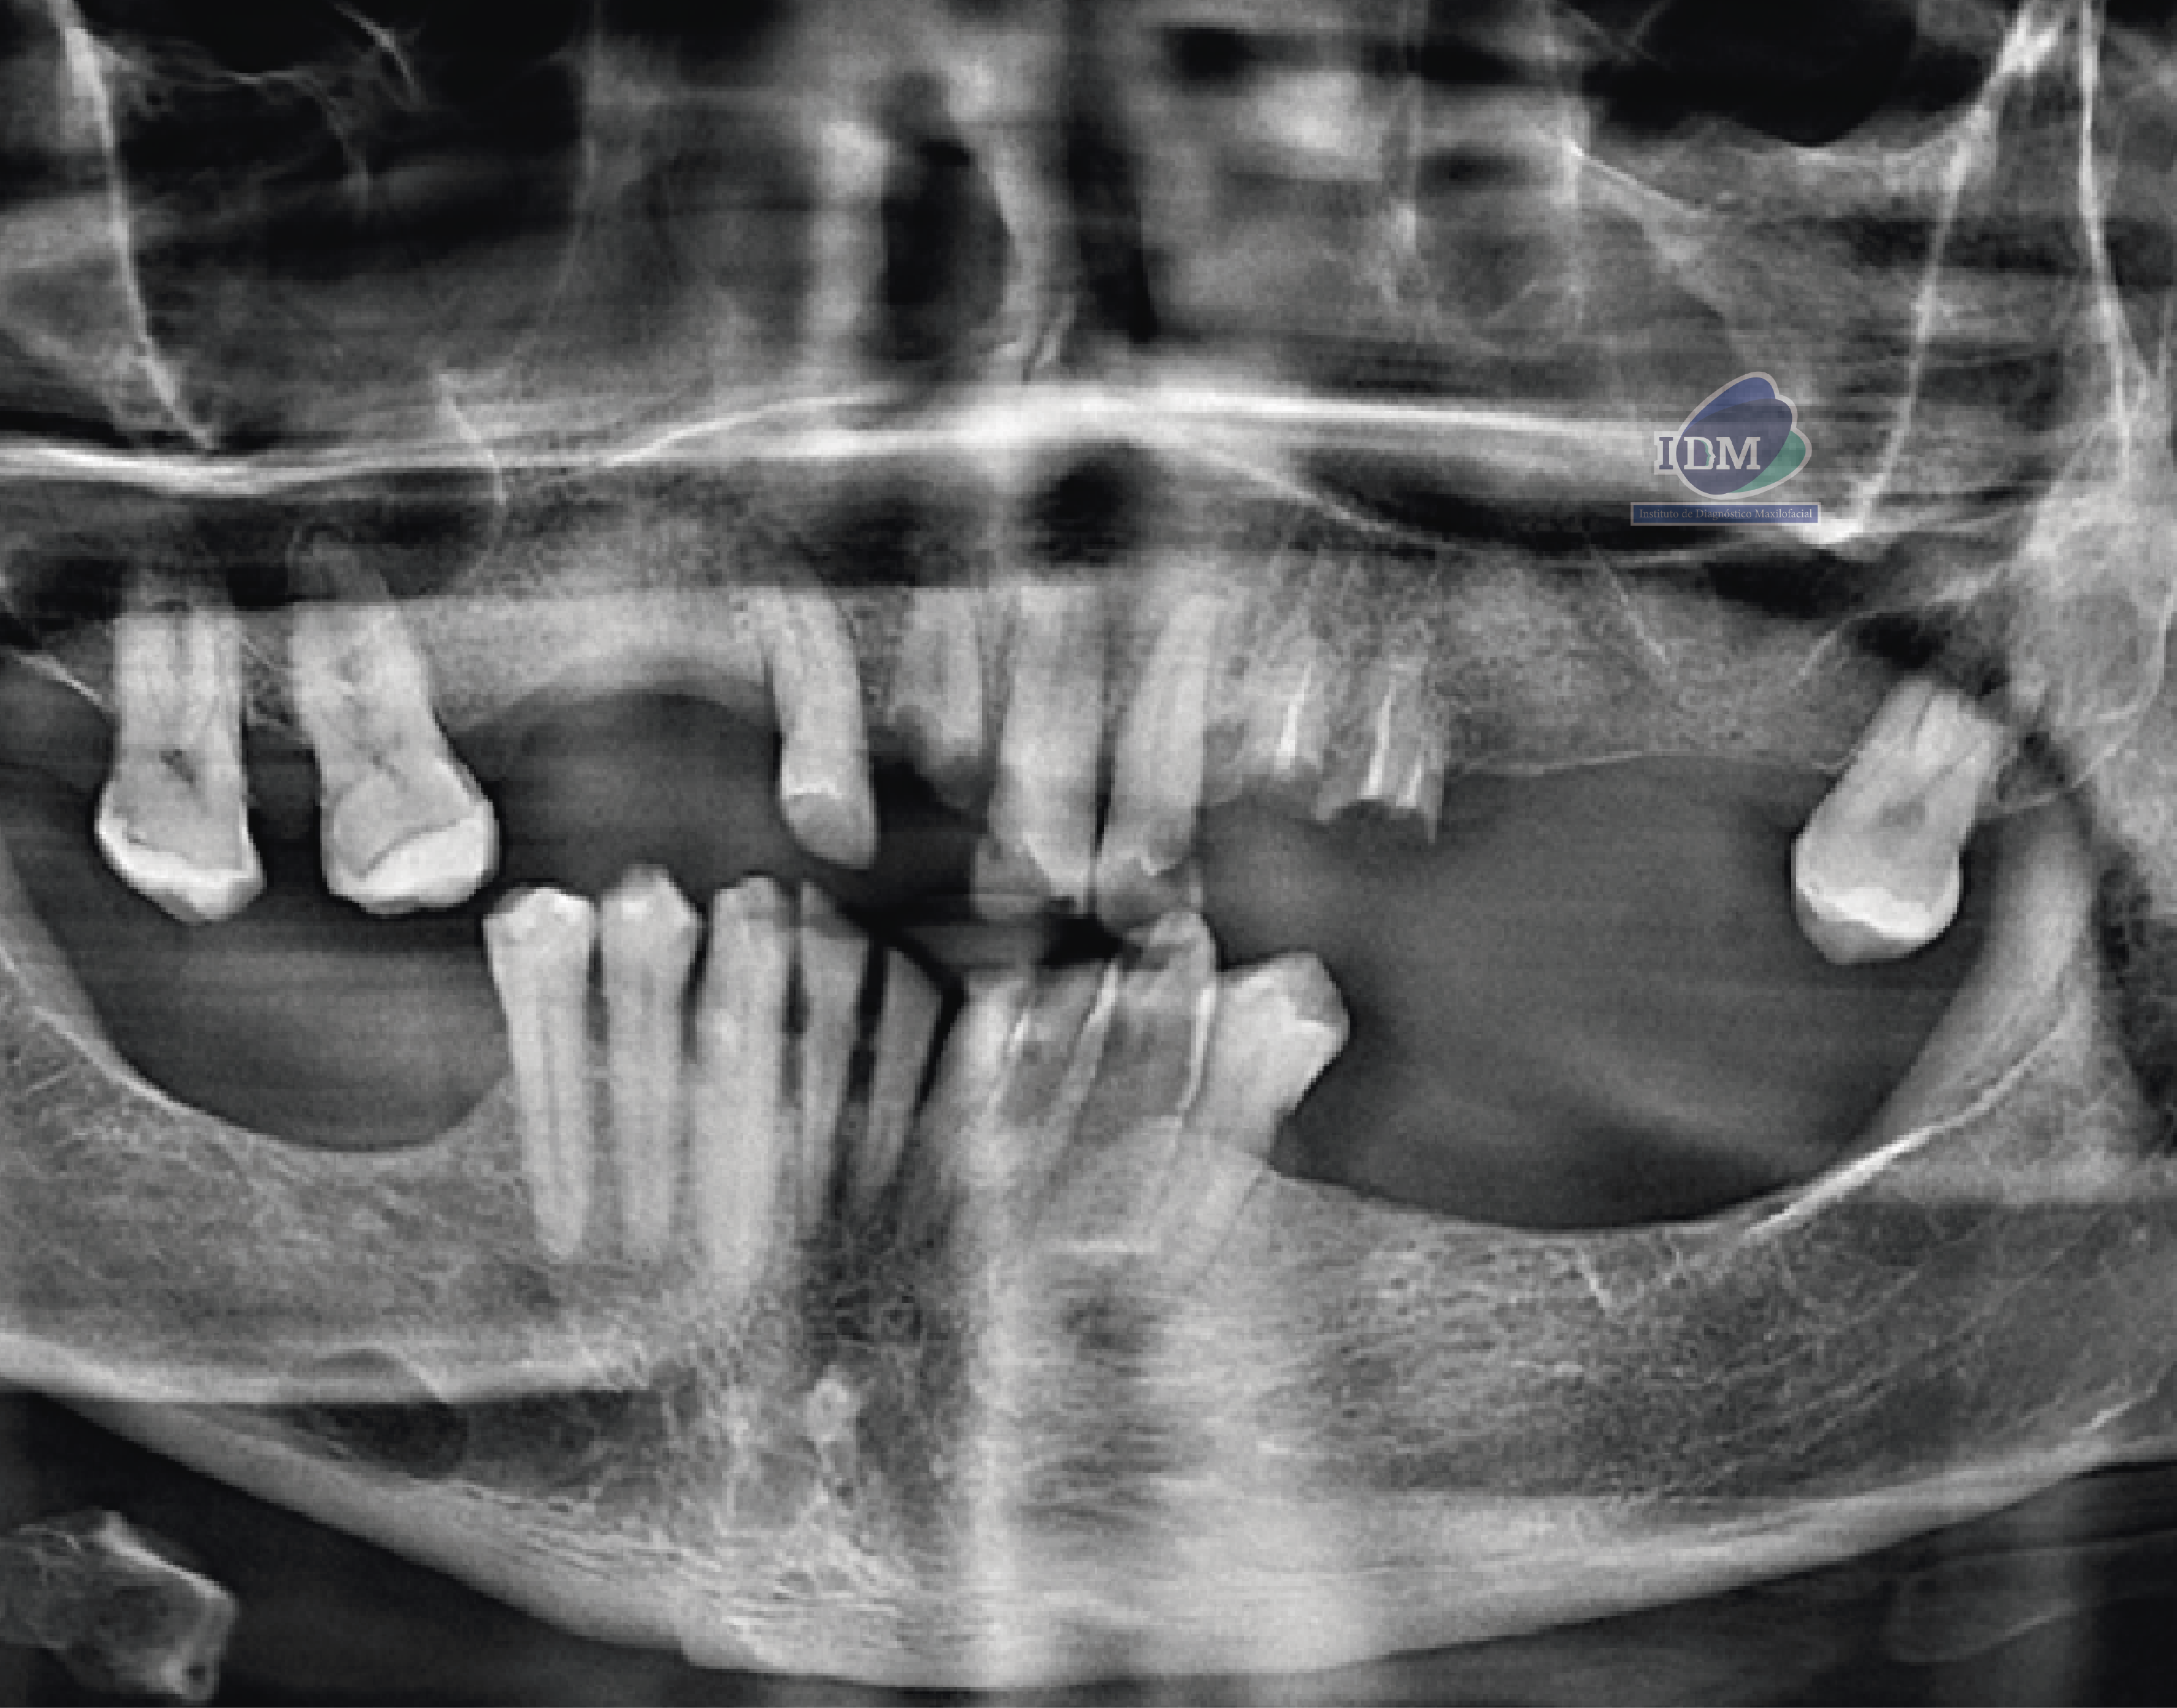

Paciente femenino de 87 años de edad, es referido al Instituto de Diagnóstico Maxilofacial – IDM para evaluación general.En la radiografía panorámica (Figura 1), se